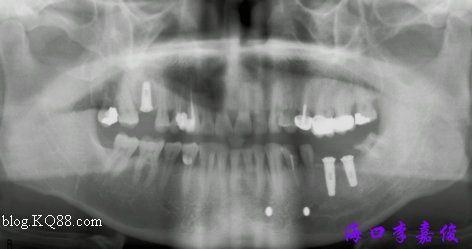

病例:患者男性、失牙數(shù)年、骨寬度與骨高度佳、上頜稍疏松。

術(shù)前全景

術(shù)后全景